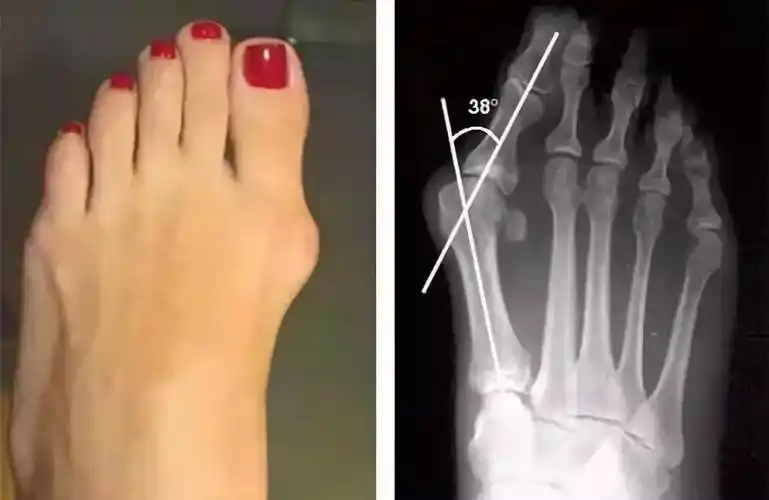

拇外翻的保守治疗